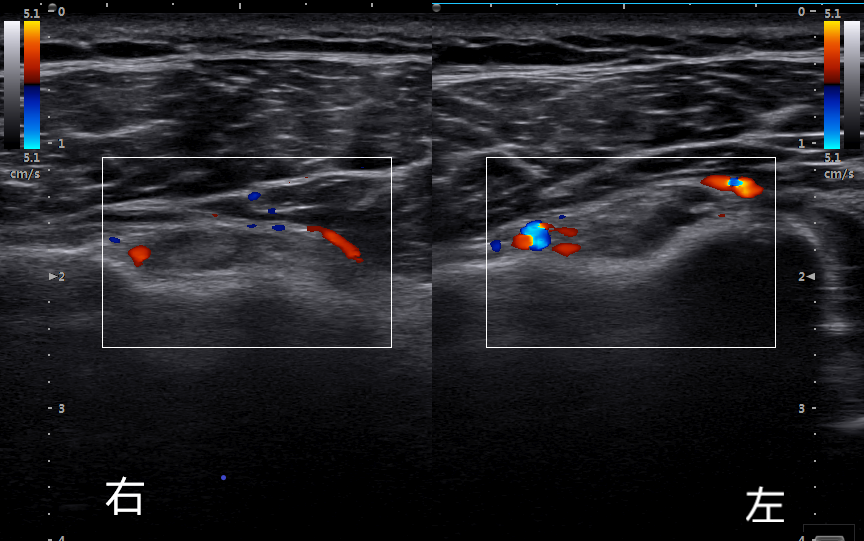

如圖彩色多普勒超聲影像所示:雙側(cè)肱二頭肌長(zhǎng)頭腱腱鞘短軸切面,血流豐富,提示存在炎癥反應(yīng)。

就診當(dāng)日予以超聲引導(dǎo)下雙側(cè)肩關(guān)節(jié)注射,2天后(27日)來(lái)院復(fù)診,肩痛基本消失,雙肩關(guān)節(jié)活動(dòng)度恢復(fù)正常,阿公對(duì)療效非常滿(mǎn)意,面露笑容。